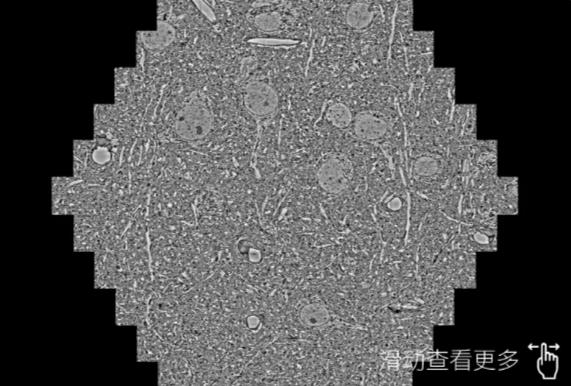

鼠脑切片。左图使用德州蔡司德州扫描电镜MultiSEM706对165μmx143pm面积区域成像,耗时仅需1.5秒。右图为鼠脑切片中30μm区域放大效果。样品由芝加哥大学B.Kasthuri提供。